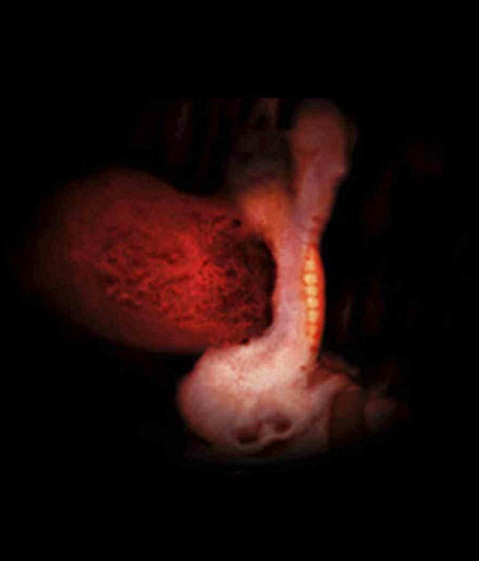

三维图

胚芽正在你的子宫深处迅速生长。这时候,宝宝的胚胎长度约0.4-0.5厘米,有一个小苹果籽大小,但是看起来还不像人,更像一只小蝌蚪。宝宝的心脏开始有规律的跳动及开始供血。

本周细胞迅速分裂,主要的器官如肾脏和肝脏开始生长。连接脑和脊髓的神经管也开始工作,原肠开始发育。胚胎的上面和下面开始形成肢体的幼芽,将来形成宝宝的手和腿。将来形成嘴巴的地方的下方有些小的皱摺,它将来会发育成宝宝的脖子和下巴。本周面部器官开始形成,鼻孔可清楚地看到,眼睛的视网膜也开始形成了。